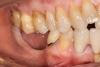

Clinical follow-ups at 2 and 7 days post- surgery were performed and did not show any complications. Sutures were removed after 14 days. During the healing period, the mesh became slightly exposed (Figure 6), and the patient was instructed to clean the exposed area with chlorhexidine on a cotton tip (twice a day) to keep the area clean.

Fig 6. Clinical observation at re-entry (5.5 months after grafting) showing exposure of the mesh.

Figure 6